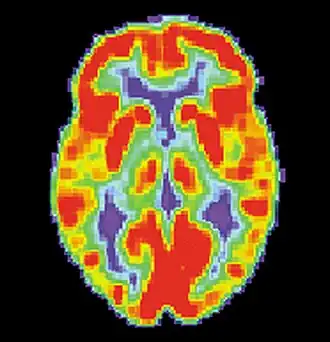

False memories and PET scans

A follow-up to the previous research was conducted by Daniel L. Schacter and colleagues. Similar to the study by Henry L. Roediger and Kathleen McDermott, subjects were read a list of associated words before they went into the PET scanner. During the first scan, subjects would make recognition judgments to determine what were the previous presented words.[2] During the second scan, subjects had to make judgments about words that were not presented. For example: bed, rest, dream, tired, and awake would be in the list but not the word "sleep". As with the study by Henry L. Roediger and Kathleen McDermott, subjects claimed to remember similar amounts of non-presented words as they did the words that were actually presented.[2] The researchers noted that brain activity during the true and false recognition tasks were very similar. Monitoring the blood flow in the brain revealed there were in the left medial temporal lobe for both veridical and illusory recognition.[17]

That is not to say that there were not differences. While monitoring blood flow in the brain during false recognition, a part of the frontal lobe that is thought to be a key monitor of memories actually showed greater activity when presented with a false recognition than with a true one.[2] There seemed to be some discrepancy as subjects attempted to scrutinize the out-placed words, but were overcome by powerful memory illusion.[2] This study demonstrates the ability of technology to help researchers understand to a greater extent the power of false memories.